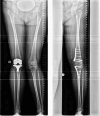

Results: The follow-up period was 24 (6-81) months. The follow-up rate was 73% (27/37). The preoperative leg axis in group one showed an average valgus of 15.9° (9-40°). Group two had an average varus of 12° (8-21°). Postoperatively, the leg axis was 3.4° varus in group one and 0.5° valgus in group two. The mLDFA changed in group one from 83.2° to 90.9°, the MPTA from 95.5° to 87.0°. In group two, the mLDFA changed from 91.9° to 85.9° and the MPTA from 83.3° to 88.3° on average. The JLCA changed in group one from - 3.2 (- 5°-0°) to - 0.5° (- 3-2°) postoperative and in group two from 3.3° (1-8°) to 3.0° (0-6°) postoperative. Tegner score, Lysholm score and Japanese knee Society score all improved significantly in both groups. Patients with a valgus axis have worse clinical scores before surgery than the varus group, but the varus group shows a higher potential for improvement postoperatively. Every patient stated that they would have the operation performed again. Complications were rare, two overcorrections required corrective surgery. Two hinge fractures were treated intraoperatively with additional contralateral plate osteosynthesis.

Conclusions: Patients show very good clinical results after DLO. The improvements in the valgus knees are greater, but starting from a lower preoperative level, probably due to improvements in both the lateral compartment and the patellofemoral compartment. An important finding was that JLCA is normalizing in valgization DLO but not in varization DLO. This needs to be considered in planning a DLO.